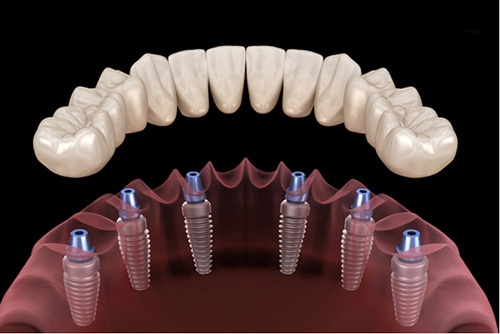

Zirkonyum kuron, olağanüstü gücü ve estetik nitelikleriyle bilinen bir malzeme olan zirkonyum oksitten yapılan bir diş kuronu türüdür. Bu kuronlar hasarlı, çürümüş veya zayıflamış dişleri kaplamak, şekillerini, boyutlarını ve işlevlerini geri kazandırmak için kullanılır. Ayrıca diş implantı restorasyonunun bir parçası olarak veya rengi solmuş veya şekilsiz dişlerin görünümünü iyileştirmek için de kullanılabilirler.

- Diş İmplantları: Eksik bir dişin yerini almak için bir diş implantının üzerine yerleştirilen bir kron olarak.

- Kuron Yerleştirme: Kuron hazır olduğunda, hazırlanan dişin üzerine yapıştırılarak işlevi ve görünümü geri kazandırılır.